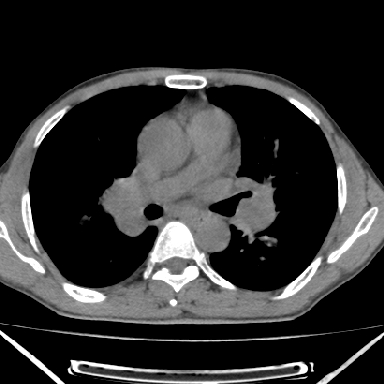

以下是引用zjzjr在2007-3-23 17:24:00的发言:[br]双侧肺门淋巴结明显肿大,以左侧为著,支气管受压变窄,肺内可见结节状及絮状高密度影,边缘模糊.考虑淋巴瘤肺内浸润.